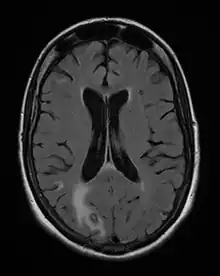

- Toxoplasmosis aguda adquirida o reactivada en el paciente inmunodeficiente, las formas clínicas más graves, incluyendo leucemia, enfermedades del tejido conectivo, los cuales pueden manifestarse en un 40 % de pacientes con sida, por ejemplo.[20] Los pacientes con terapias inmunosupresoras (glucocorticoides, por ejemplo) como para prevenir el rechazo de un órgano trasplantado o el tratamiento de una enfermedad autoinmunitaria, pertenecen a este grupo de alto riesgo.

Otros métodos indirectos incluyen reacciones de fijación de complemento, reacción con colorantes de Sabin y Feldman, pruebas de ELISA y la reacción de hemaglutinación indirecta. Es posible también demostrar la presencia del genoma del parásito con la técnica de PCR, un método importante debido a su alta sensibilidad y especificidad,[24] pues siempre que es positivo confirma el diagnóstico pero si es negativo no siempre lo excluye. El método de detección por PCR se utiliza en el diagnóstico de toxoplasmosis en el líquido amniótico, en el humor acuoso en toxoplasmosis ocular y en inmunosuprimidos.[26] La detección directa del parásito en tejidos infectados puede también resultar difícil, por ejemplo, de placenta o cerebro, incluyendo la fijación de anticuerpos fluorescentes.